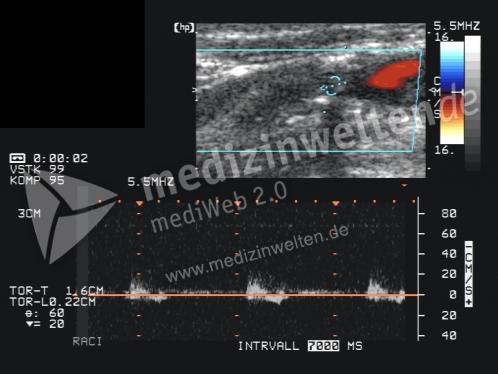

Arteria Carotis Interna

Stenose der Arteria carotis interna Pathologie/Symptome Die Entwicklung arteriosklerotischer Veränderungen an der hirnversorgenden Schlagader (Arteria carotis interna, ACI) ist eine häufige Begleiterkrankung der koronaren Herzkrankheit Typische Symptome der bedeutsamen Verengung der ACI sind "MiniSchlaganfälle" Sekundenblindheit.